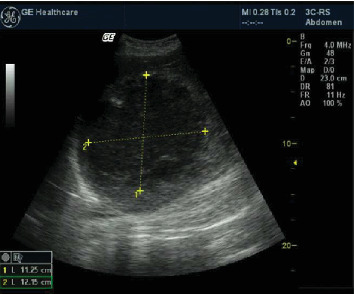

背景:疟疾和阿米巴感染被认为是死产和早产的危险因素,但它们在妊娠期间的共存尚未有报道。病例:我们描述了在布隆迪的一家农村医院发生的第一例避免产妇死亡的病例,胎儿在妊娠22周时在子宫内死亡,同时伴有恶性疟疾和肝阿米巴脓肿。结论:阿米巴肝脓肿在妊娠期间很少被描述,据我们所知,从未与严重疟疾合并:两种寄生虫感染需要完全不同的治疗。我们成功地在农村地区处理了这个困难的病例,这至少要归功于三个主要因素:工作人员的技能、创造性和超声技术的进步。

Background: Malaria and amoebic infections are considered risk factors for stillbirth and preterm labor, but their coexistence during pregnancy has not been previously reported. Case: We describe the first case of averted maternal mortality with fetal death in utero at 22 weeks' gestation, complicated by both falciparum malaria and hepatic amoebic abscess, in a rural hospital in Burundi. Conclusion: Amoebic liver abscesses are rarely described in pregnancy and, as far as we are aware, never in conjunction with severe malaria: two parasitic infections requiring completely different treatments. We successfully managed this difficult case in a rural context thanks to at least three main factors: staff skills, inventiveness, and advances in ultrasonographic technology.